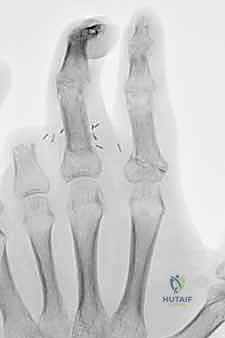

الأساس المتين هو أول خطوة في البناء. يقوم الدكتور هطيف بتقصير العظام قليلاً (Bone Shortening) لتخفيف الشد على الأوعية الدموية والأعصاب عند توصيلها. يتم تثبيت العظام باستخدام أسلاك كيرشنر المعدنية (K-wires)، أو مسامير دقيقة، أو صفائح معدنية صغيرة. التثبيت يجب أن يكون قوياً ليسمح ببدء العلاج الطبيعي المبكر.